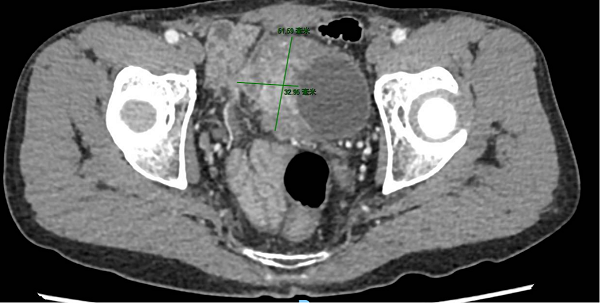

术前影像提示膀胱右侧壁巨大肿瘤,侵犯腹膜及膀胱外脂肪组织